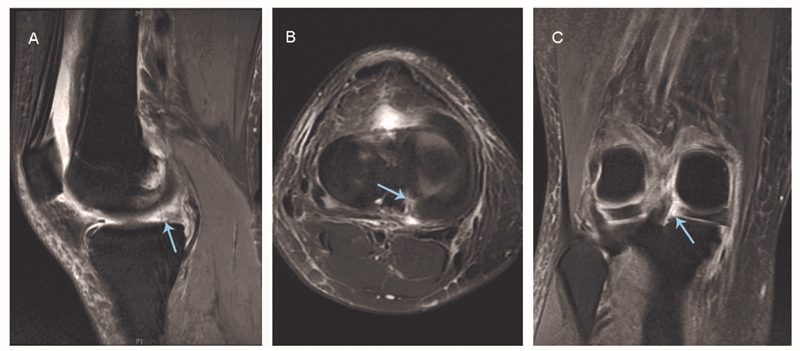

图1 磁共振成像显示内侧半月板后根撕裂

A:矢状位无正常半月板信号:鬼影征(箭头所示);B:轴位图像显示内侧半月板后根部放射状线形缺损(箭头所示);C:冠状位表现为内侧半月板后内缘走形突然中断(箭头所示)